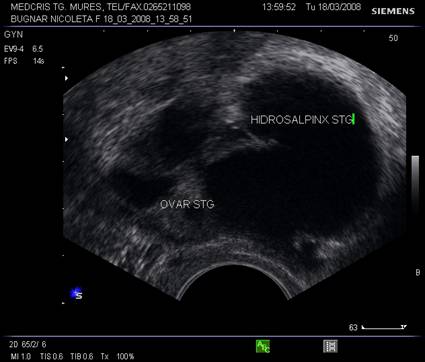

Fig. nr. 404. Colectie anecogena in lumenul trompei .Hidrosalpinx ce inconjura ovarul omonim, se remarca peretele cudat al trompei cu continut lichidian.